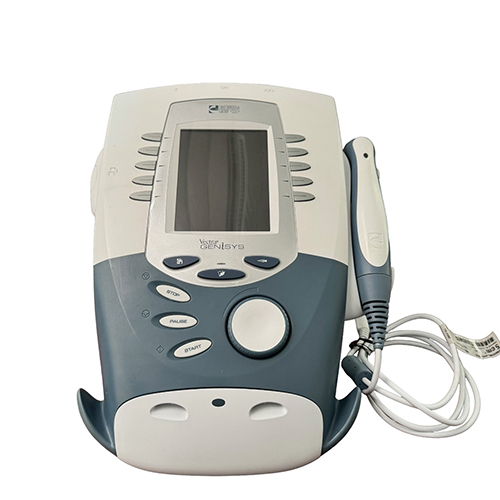

We use World-class Equipments to help you with the best treatment & recover faster

Wirless Pro

Electrotherapy